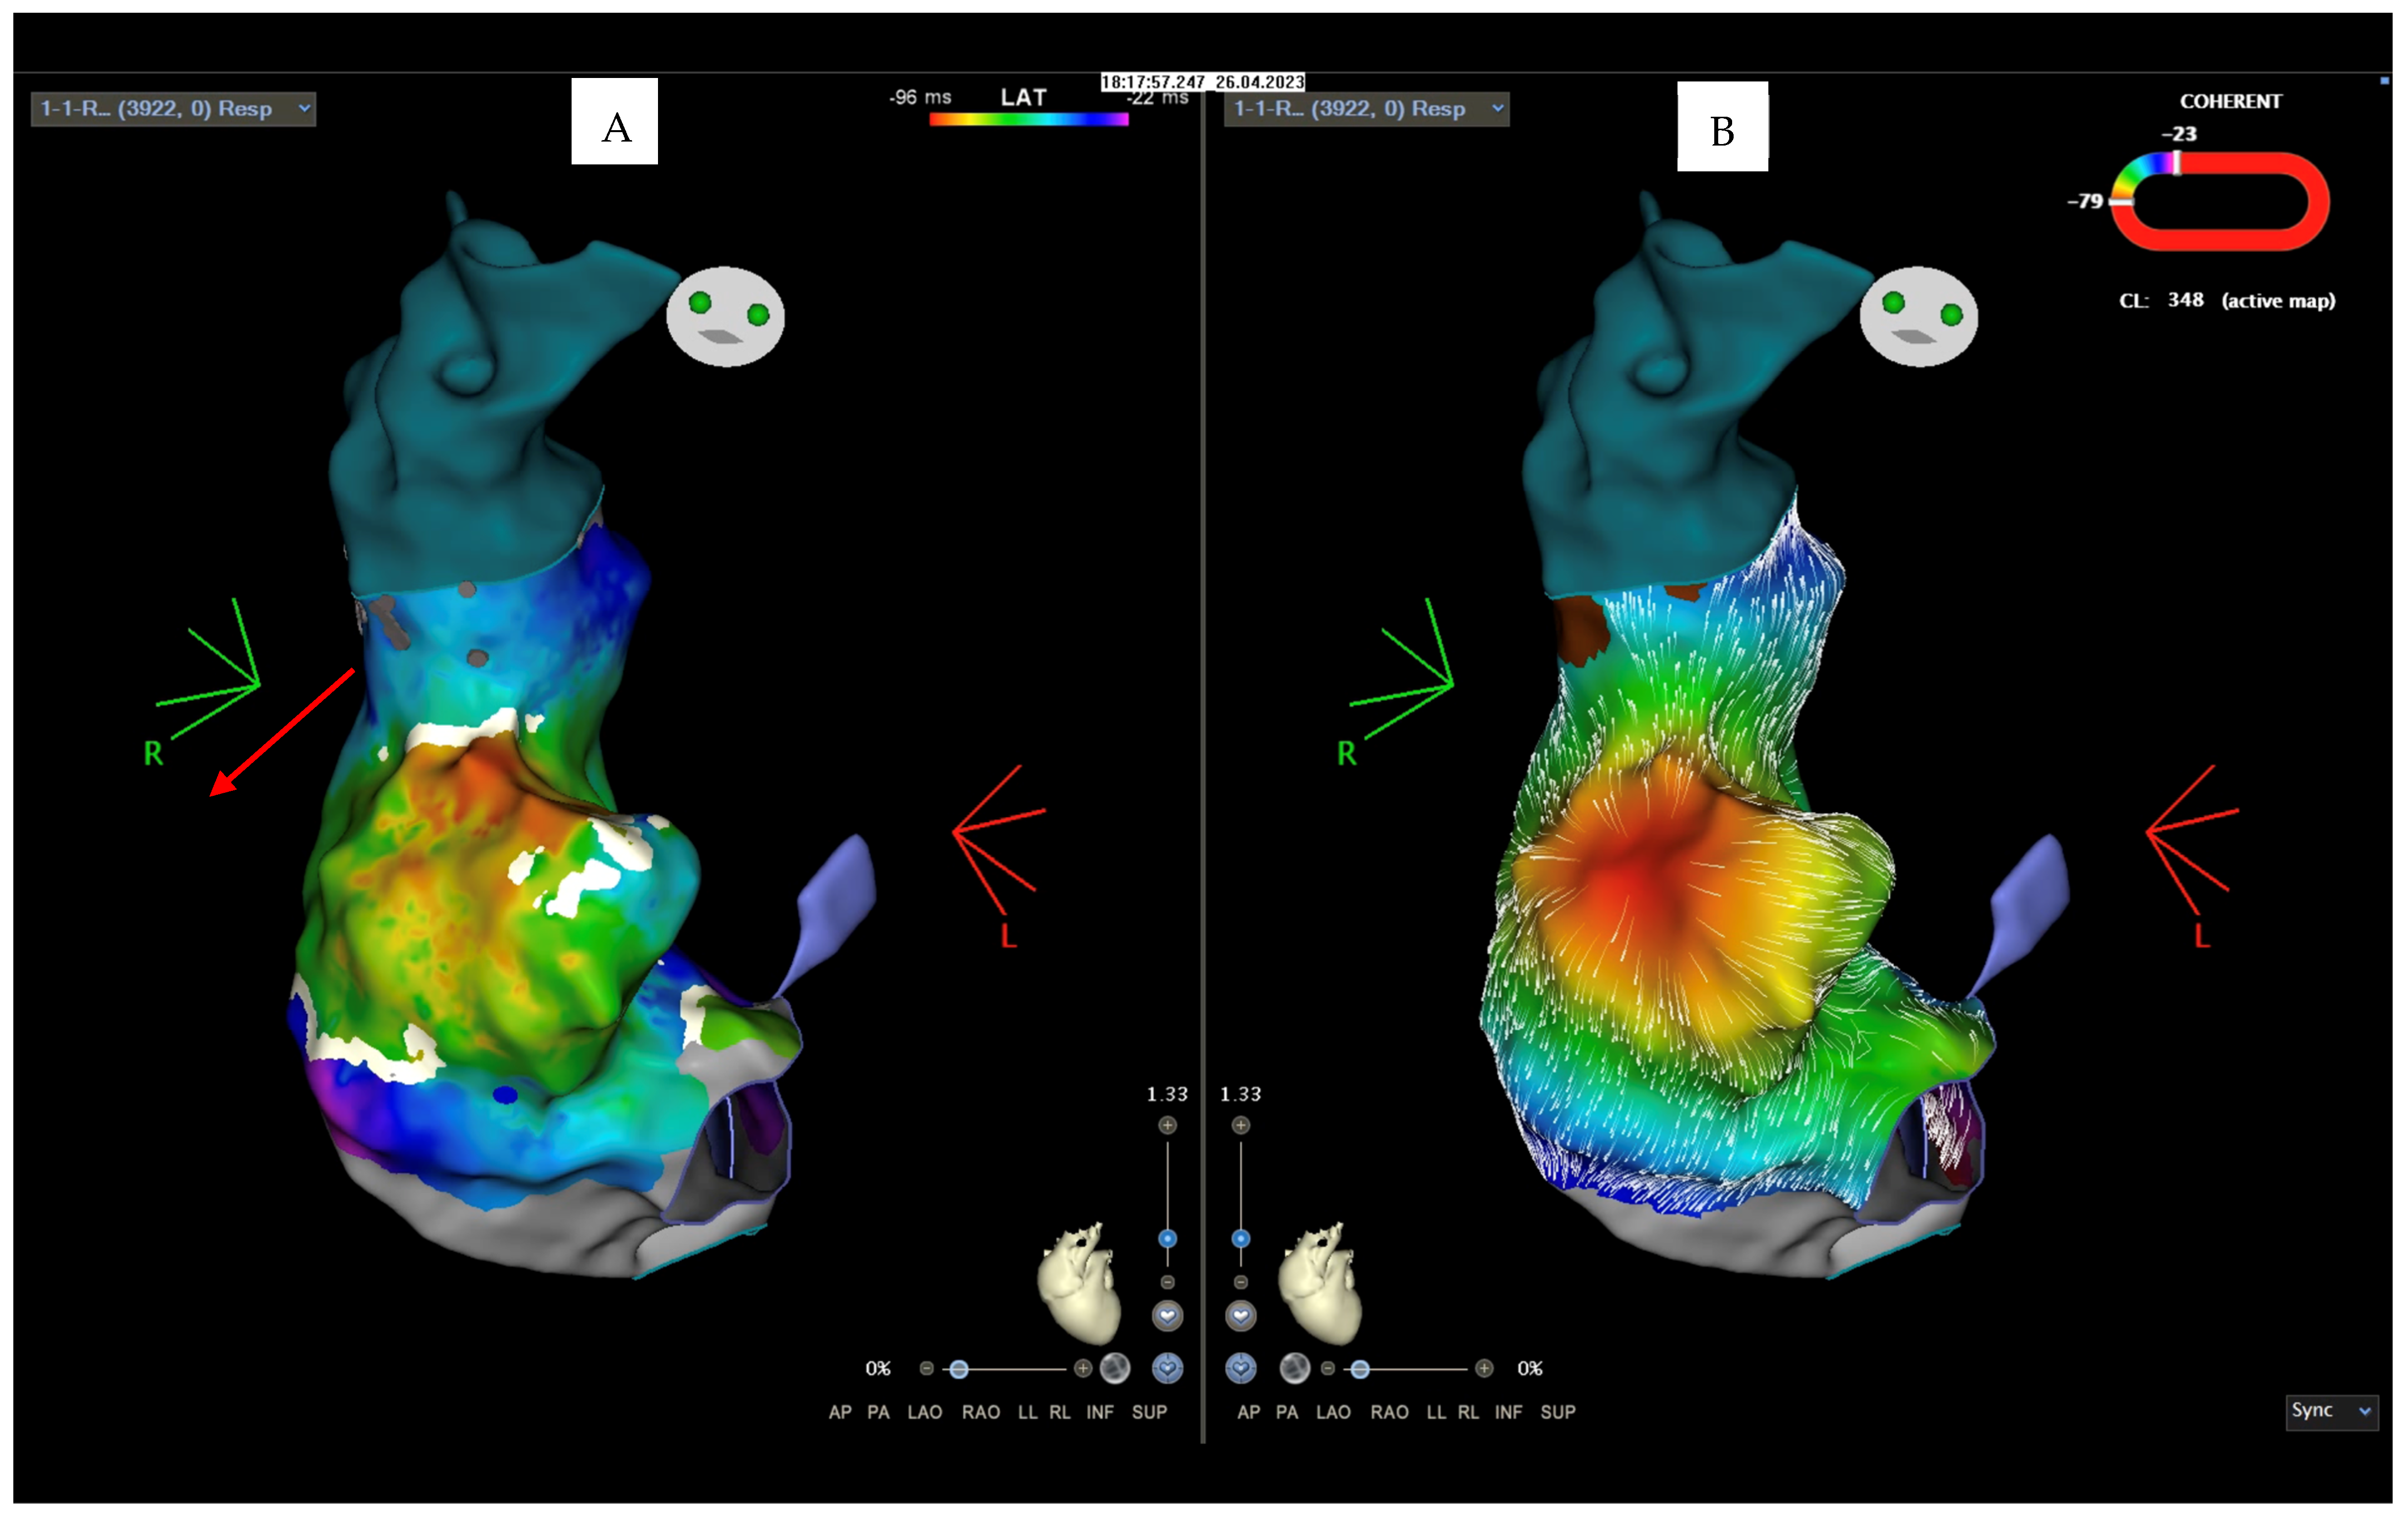

2. Case Description